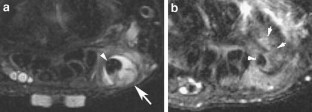

Results

Five of the patients showed evidence of triscaphe osteoarthritis. One of the patients showed synovitis and reactive marrow edema at the triscaphe joint without more specific findings of osteoarthritis. Five patients showed evidence of FCR tenosynovitis. Partial-thickness tears were noted in three patients. Two patients showed complete discontinuity of the FCR; one of them had undergone prior tendon harvesting for interposition arthroplasty after trapezectomy. One patient showed a ganglion cyst in connection to the FCR tendon sheath.

The FCR tendon courses over the volar surfaces of the scaphoid and trapezium in a separate fibro-osseous tunnel. This anatomical and functional relationship explains the coexistence of FCR tendinopathy and STT arthritis demonstrated by MR imaging.